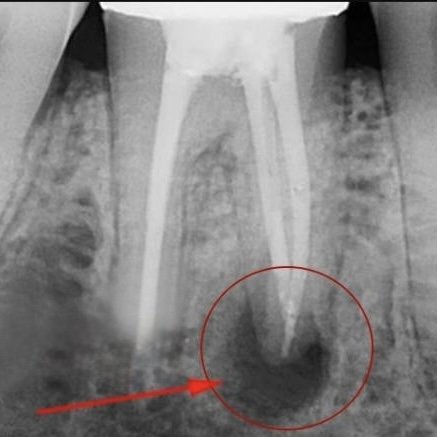

- ▪ кіста або гранульома на верхівці кореня не зникає після повторного ендодонтичного лікування. У таких випадках консервативні методи виявляються неефективними, і запальний процес продовжує прогресувати. Хірургічне видалення уражених тканин стає єдиним способом усунути джерело інфекції та запобігти подальшому руйнуванню кісткової тканини.

- ▪у пацієнта є хронічний періодонтит, який не піддається консервативному лікуванню. Постійне запалення призводить до руйнування тканин, що оточують корінь зуба. Резекція допомагає усунути осередок інфекції, зупинити запальний процес та зберегти зуб від видалення.